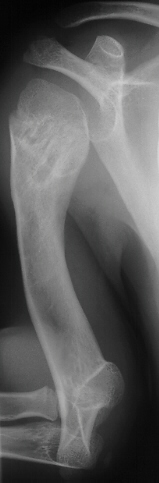

This 3 year boy presented with shortening of the right humerus.

Clinical examination revealed 4 cm shortening of right arm and

painless limitation of ROM of right shoulder; abduction was 150

degrees with 80 degrees at the glenohumeral joint and internal

rotation was significantly limited(image 1). There was also a

of the same knee(image 2). Radiological examination showed absence

of proximal epiphysis of the right humerus(image 1)with marked

deformity of the metaphyseal region. By age 11 the child had a